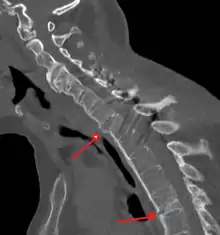

Lateral X-ray of the neck in ankylosing spondylitis

CT scan showing bamboo spine in ankylosing spondylitis